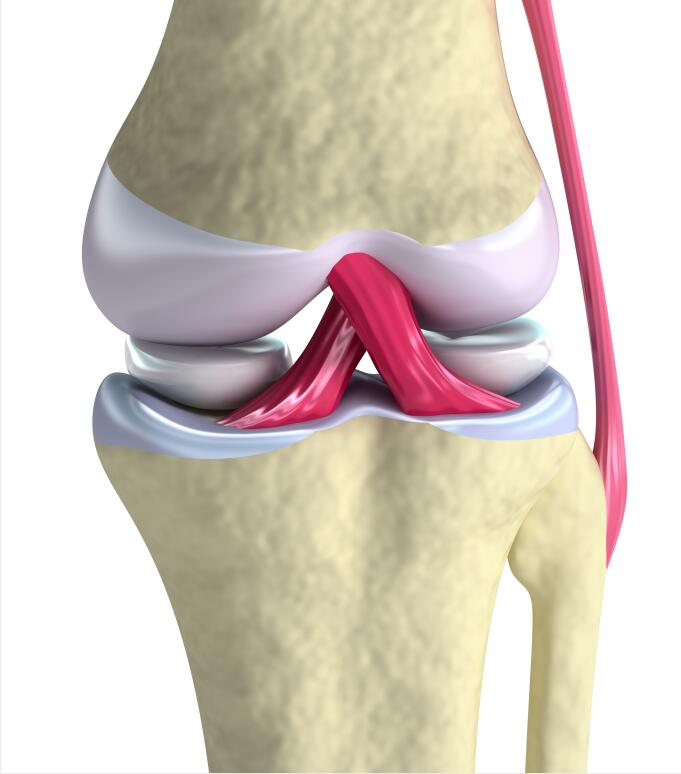

在说明这个问题之前,我们先一起来了解一下我们人体膝关节的主要构造,这是一个人体膝关节的模型,人体的膝关节是由上方的大腿骨股骨,下方小腿骨胫骨、腓骨,还有前方的髌骨构成。骨质的稳定性除了由肌肉和关节囊保证以外,还有侧方的内侧副韧带,外侧副韧带来维持它的侧方稳定,另外我们膝关节的中央,还有前后交叉走行的交叉韧带来维持小腿骨,也就是胫骨前后向的稳定,同时交叉韧带还有一个重要的功能,就是维持膝关节在屈伸活动过程中,它的股骨相对于胫骨的一个正常运动轨迹。

在股骨、胫骨之间,还有一个增加关节面吻合度的半月板,内侧半月板和外侧半月板,在一般正常的情况下,我们膝关节的负重力线是通过膝关节的正中央的,由于人体膝关节的构造的特点,造就了我们膝关节内侧间隙,它的负重要多于外侧,数据研究统计显示,内侧间隙的负重,应该是占到整个膝关节负重的60%。